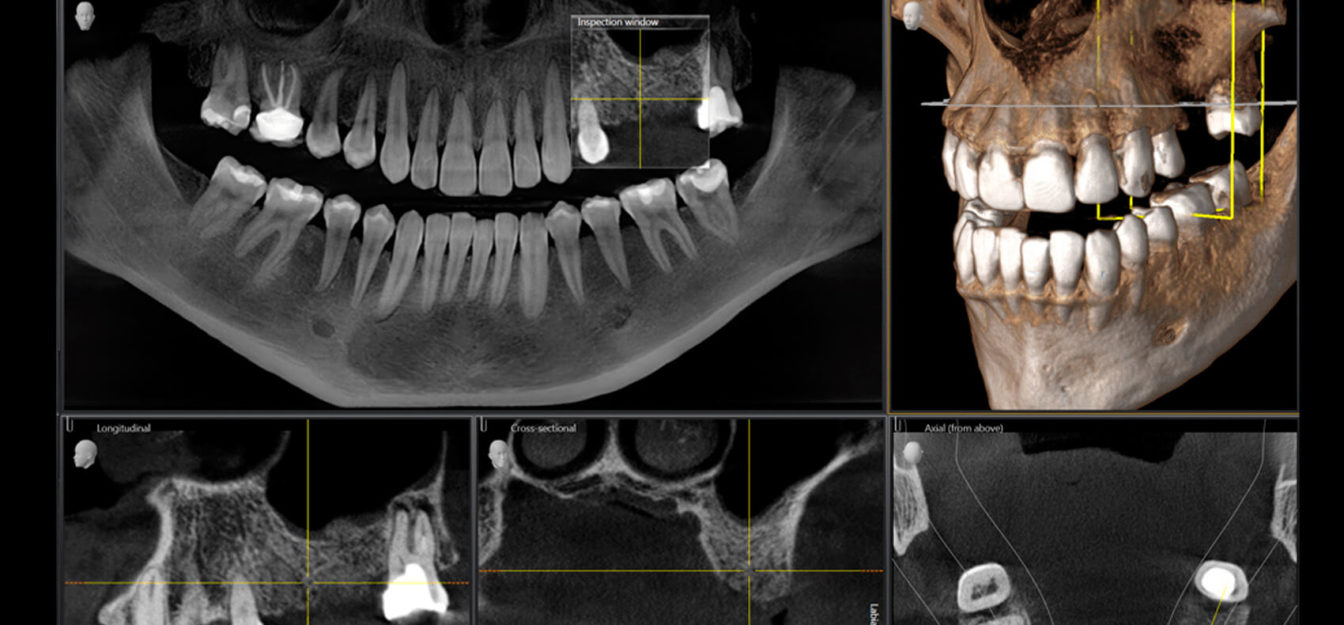

Процесс начинается с точного цифрового сканирования полости рта пациента․ Для этого используются внутриротовые сканеры, которые создают трехмерную модель челюсти с высокой степенью детализации․ Эти сканеры, в отличие от традиционных методов снятия слепков, обеспечивают более точное и быстрое получение данных, минимизируя дискомфорт для пациента․ Полученная цифровая модель импортируется в специализированное программное обеспечение CAD (Computer-Aided Design), где опытный техник-протезист может виртуально моделировать будущий протез, точно подбирая его форму, размер и цвет, учитывая индивидуальные анатомические особенности пациента․

На этом этапе происходит виртуальное планирование всех этапов изготовления протеза․ Протезист может визуализировать финальный результат, вносить корректировки и моделировать различные варианты протеза до начала его физического изготовления․ Это позволяет значительно снизить риск ошибок и обеспечить высокую точность конечного продукта․